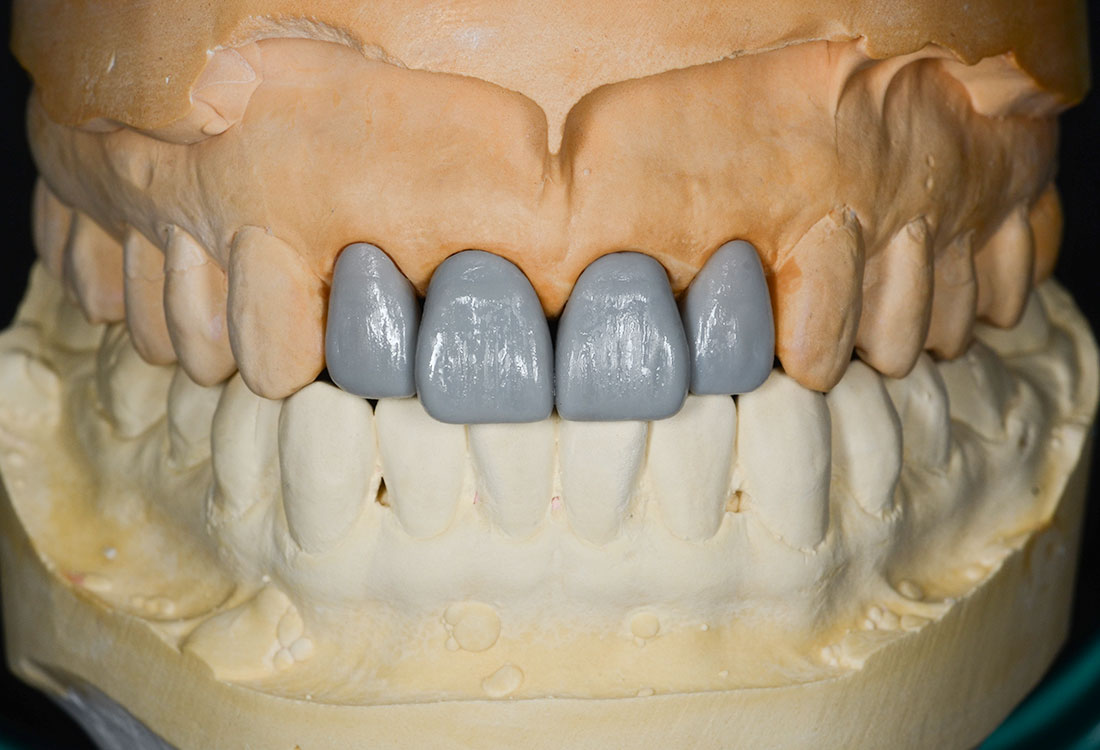

模型を作成して最終的な形を模索します。

土台になる歯の形を整えて最終的な形の模型を作ります。